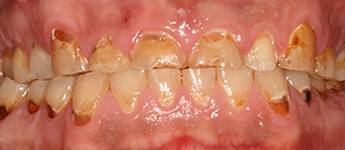

10. eset

Savas kémhatású anyagok, mint például a szénsavas üdítők túlzott használata is a fogak zománcrétegének nagyfokú károsodását okozhatják. 35 éves férfi páciensnek készítettünk a frontfogaira Zirkon koronákat, a rágófogaira pedig fémkerámia szóló koronákat. 28 koronával állítottuk helyre a fogazatot.